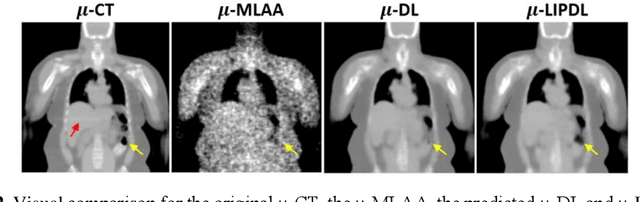

Abstract:In PET/CT imaging, CT is used for PET attenuation correction (AC). Mismatch between CT and PET due to patient body motion results in AC artifacts. In addition, artifact caused by metal, beam-hardening and count-starving in CT itself also introduces inaccurate AC for PET. Maximum likelihood reconstruction of activity and attenuation (MLAA) was proposed to solve those issues by simultaneously reconstructing tracer activity ($\lambda$-MLAA) and attenuation map ($\mu$-MLAA) based on the PET raw data only. However, $\mu$-MLAA suffers from high noise and $\lambda$-MLAA suffers from large bias as compared to the reconstruction using the CT-based attenuation map ($\mu$-CT). Recently, a convolutional neural network (CNN) was applied to predict the CT attenuation map ($\mu$-CNN) from $\lambda$-MLAA and $\mu$-MLAA, in which an image-domain loss (IM-loss) function between the $\mu$-CNN and the ground truth $\mu$-CT was used. However, IM-loss does not directly measure the AC errors according to the PET attenuation physics, where the line-integral projection of the attenuation map ($\mu$) along the path of the two annihilation events, instead of the $\mu$ itself, is used for AC. Therefore, a network trained with the IM-loss may yield suboptimal performance in the $\mu$ generation. Here, we propose a novel line-integral projection loss (LIP-loss) function that incorporates the PET attenuation physics for $\mu$ generation. Eighty training and twenty testing datasets of whole-body 18F-FDG PET and paired ground truth $\mu$-CT were used. Quantitative evaluations showed that the model trained with the additional LIP-loss was able to significantly outperform the model trained solely based on the IM-loss function.